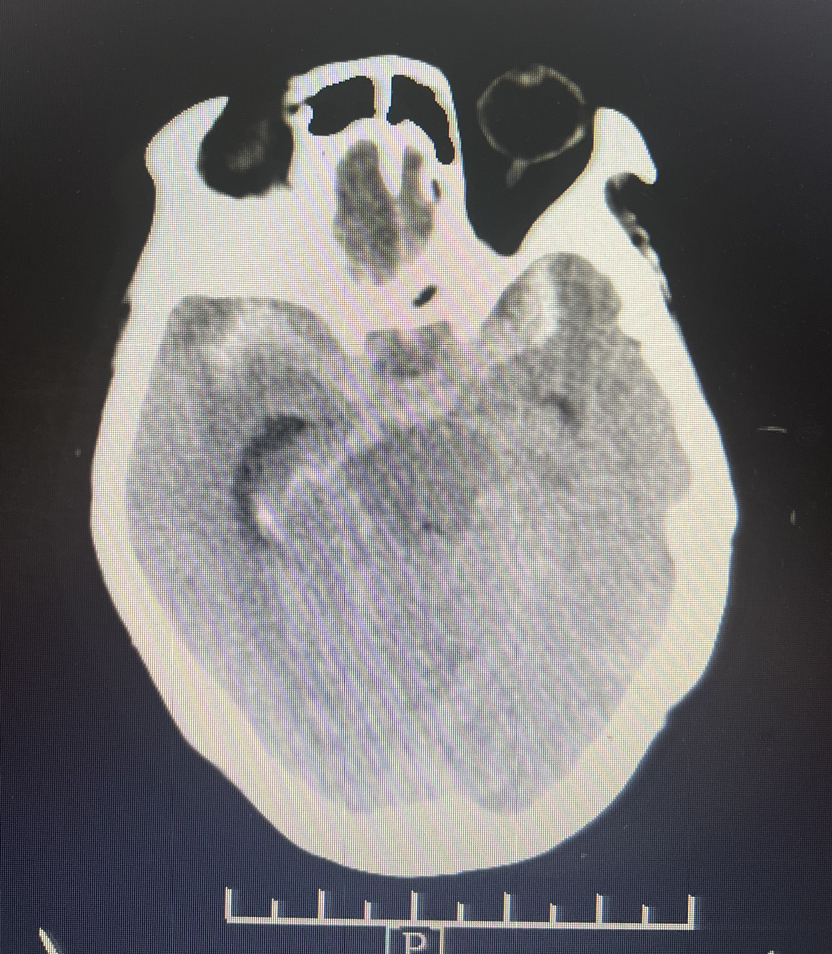

4、急诊CTA:

DSA:双侧大脑前动脉A1段存在,右侧A1段与前交通动脉结合处囊状凸起,最大径约2.8m m